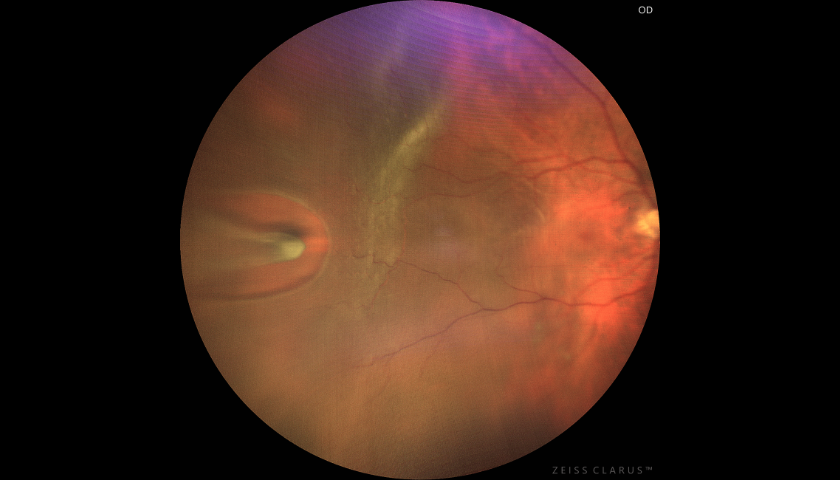

A Membrana Epirretíniana corresponde a uma fina e quase transparente película de material celular fibroso que se desenvolve como um “filme” sobre a mácula.

Estas Membranas pelas suas características físicas exercem uma tração irregular sobre a mácula alterando a sua organização interna e comprometendo a função visual de uma forma progressiva.

Trata-se de uma fina camada de tecido fibroso sobre a superfície da mácula. Esta Membrana, ao contrair, exerce uma tração sobre o delicado tecido retiniano subjacente co prometendo de forma progressiva a função visual.